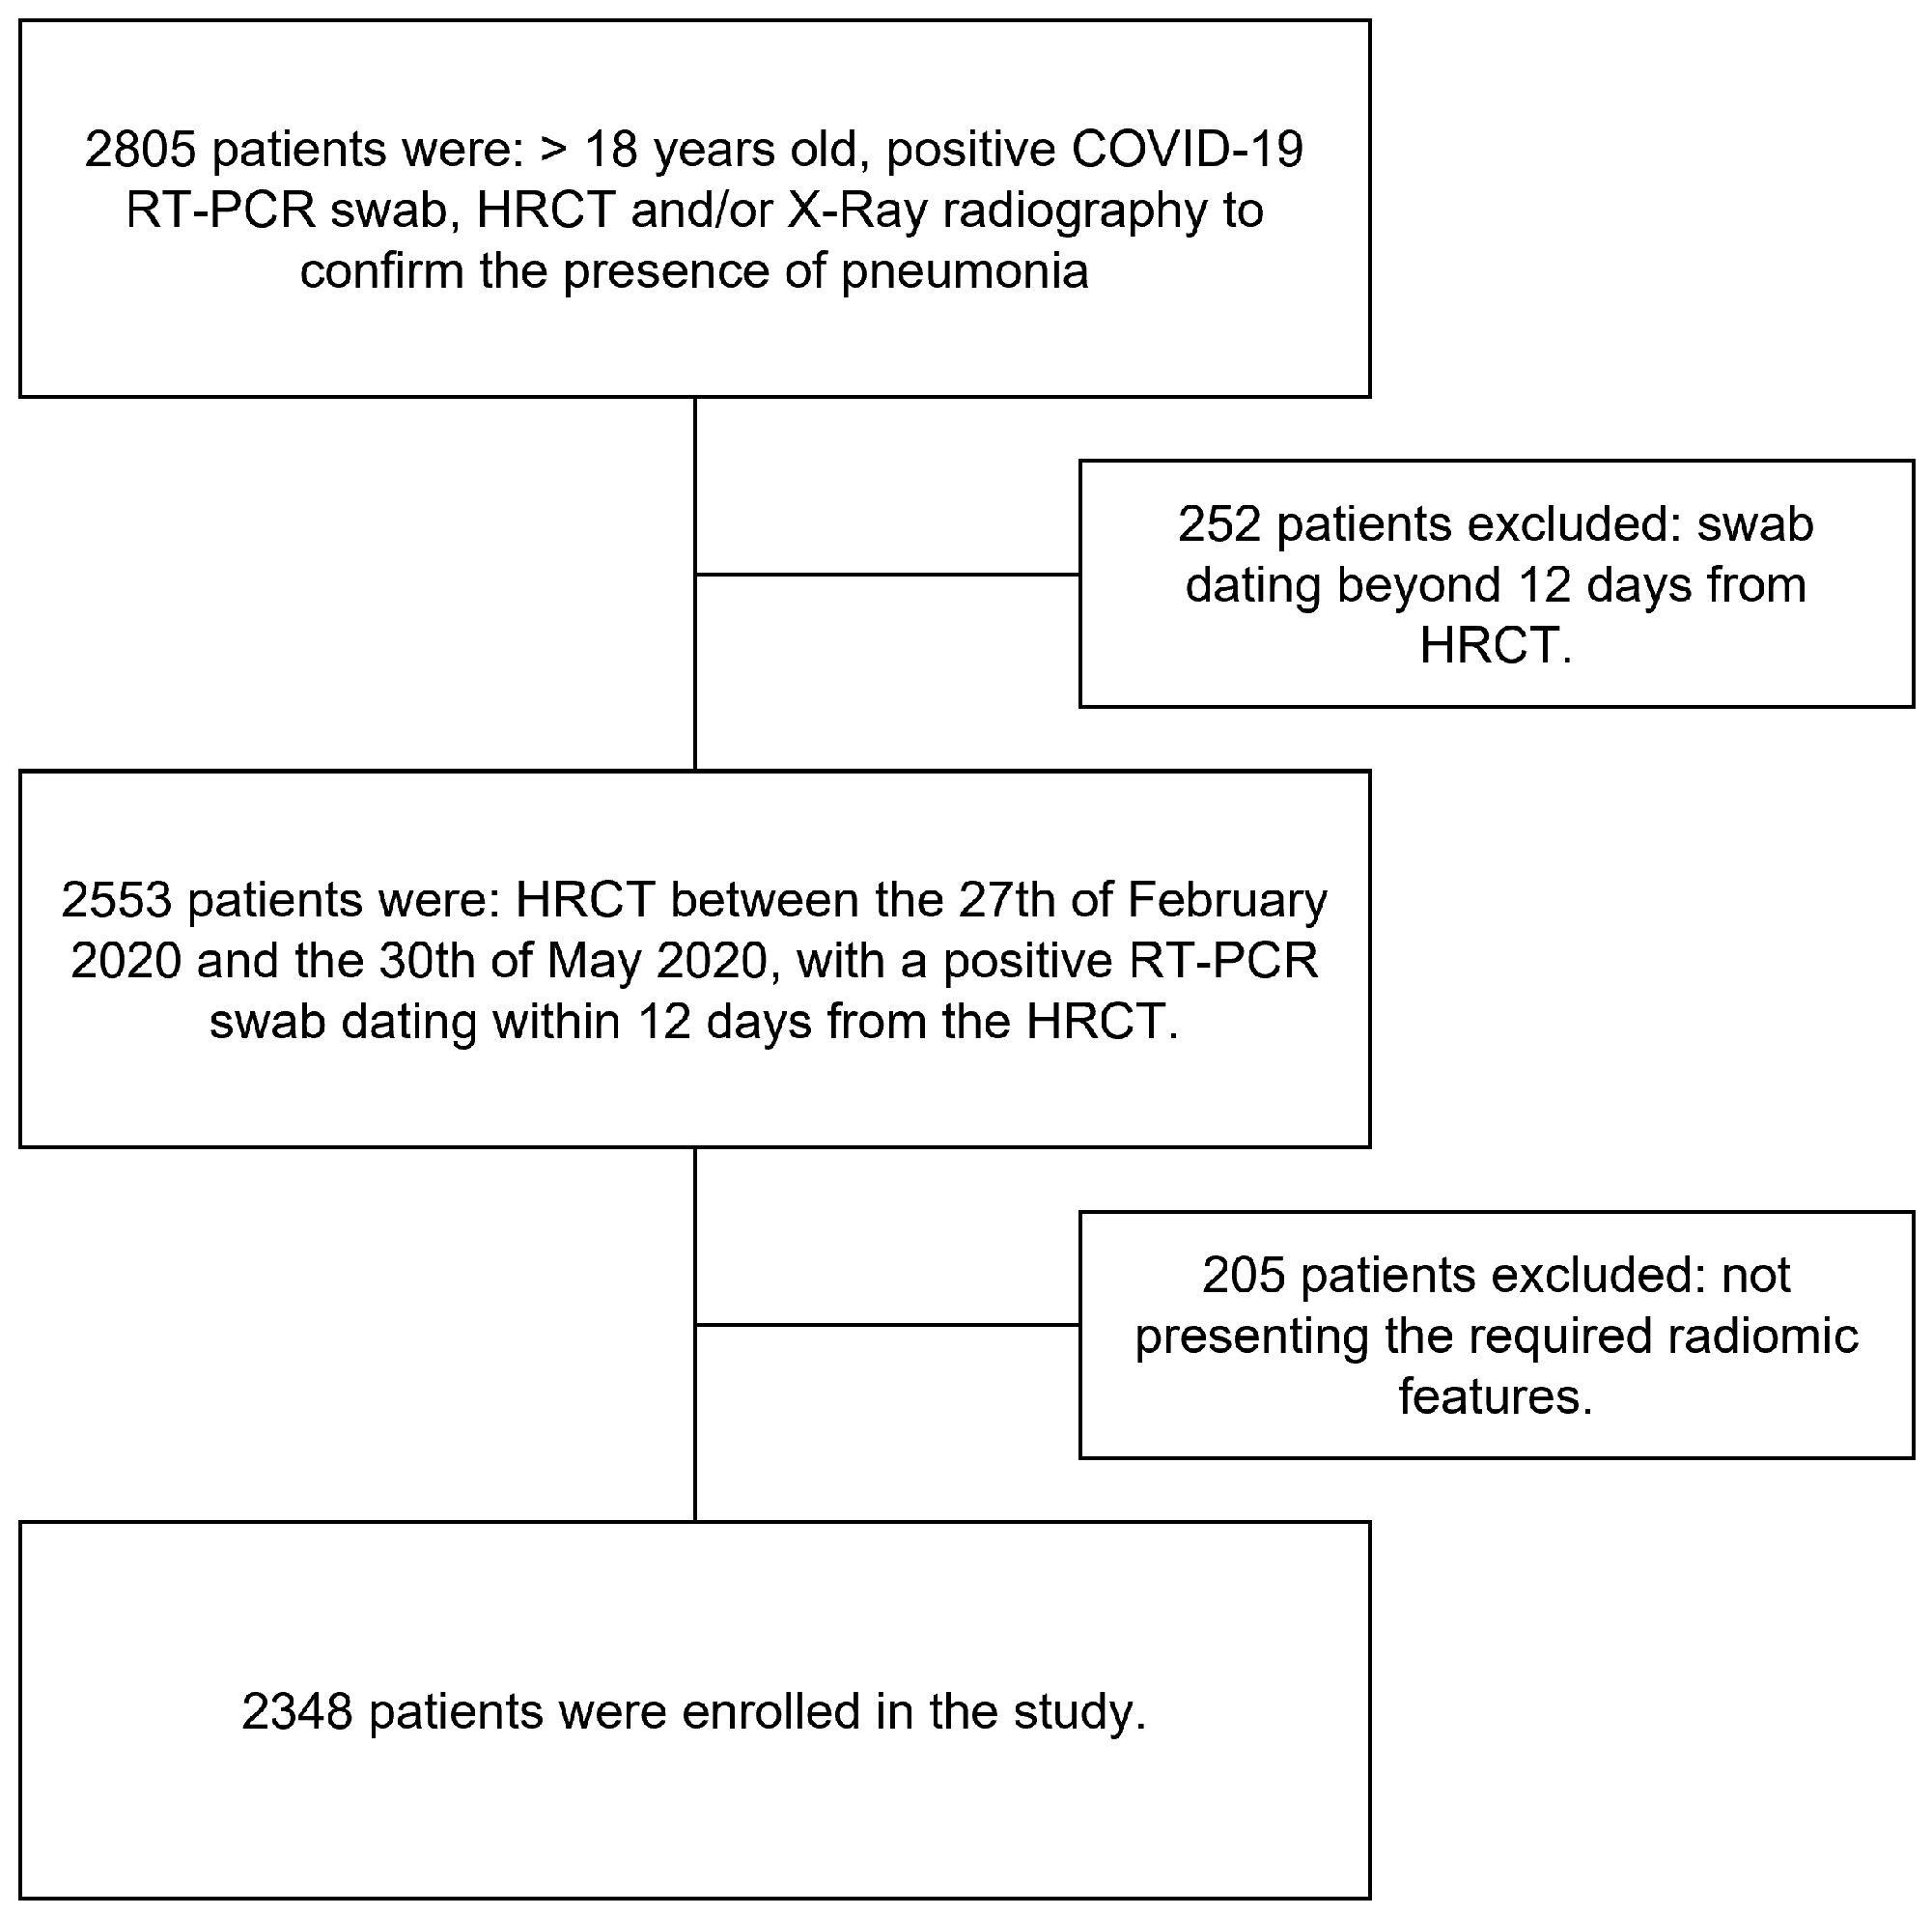

2.1. Study Population